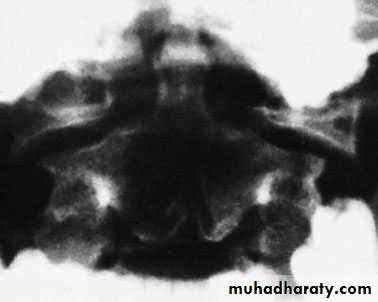

C1 ring fracture

Sudden severe load on the top of the head may cause

a ‘bursting’ force which fractures the ring of the atlas

(Jefferson’s fracture). There is no encroachment on

the neural canal and, usually, no neurological damage.

The fracture is seen on the open-mouth view (if the

lateral masses are spread away from the odontoid peg)

and the lateral view. A CT scan is particularly helpful

in defining the fracture.

Fracture of C1 ring Jefferson’s fracture – bursting